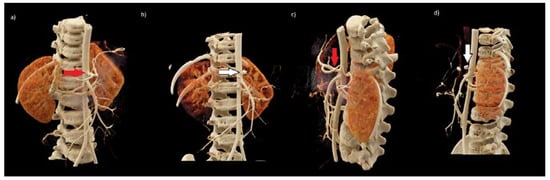

Such a dramatic complication after the neuroblastoma tumor removal procedure has not been observed in our center or in the available literature so far; therefore, radiologists were asked to re-analyze all CT images. Retrospectively performed 3D reconstruction of CT examinations allowed to precisely show the location of the tumor in relation to the large vessels in the abdominal cavity, including the abdominal trunk (Figure 2 and Figure 3). The results of CT examinations presented in this way made it possible to precisely locate the course of the vessels in relation to the tumor. Moreover, they showed vascular IDRFs present at the time of diagnosis and preoperatively. The results of computed tomography presented in this way helped us to re-analyze the previous examination without reconstruction. The listed elements were visible but less noticeable.

In the postoperative workup of this complication, 3D reconstructions were made in dedicated syngo.via imaging software for the TK Dual Source Somatom Force scanner (Siemens, Erlangen, Germany) (Figure 2 and Figure 3). The representation of the 3D reconstructions clearly showed the relationship of the tumor to the surrounding structures. They made operators aware that it was practically impossible to remove the entire lesion without damaging the coeliac trunk. The vessel entered centrally into the tumor (Figure 2). After re-examining the original study, surgeons found features so emphasized on the 3D reconstruction scans. After careful analysis, they were noticeable but much more difficult. We cannot say that 3D reconstructions are necessary every time because not every center has this kind of possibility, but they are very beneficial in preparing the surgeon for complicated operations.

Figure 2. Preoperative abdominal computed tomography (CT) scan in the arterial phase with 3D VRT reconstructions (ad), additionally visualizing the mass of the tumor (b,d). CT—coeliac trunk, SA—splenic artery, CHA—common hepatic artery, LGA—left gastric artery, SMA—superior mesenteric artery, RRA—right renal artery, LRA—left renal artery, LRV—left renal vein.

Figure 3. Preoperative (a,c) and postoperative (b,d) 3D VRT reconstructions of vessels in abdominal CT scan in the arterial phase. Red arrows (a,c)—normal variation of the coeliac trunk with its branches. White arrows (b,d) note absent depiction of the coeliac trunk and its main branches. In the typical location of the coeliac trunk, there are vascular clips; nearby next two clips are visible.